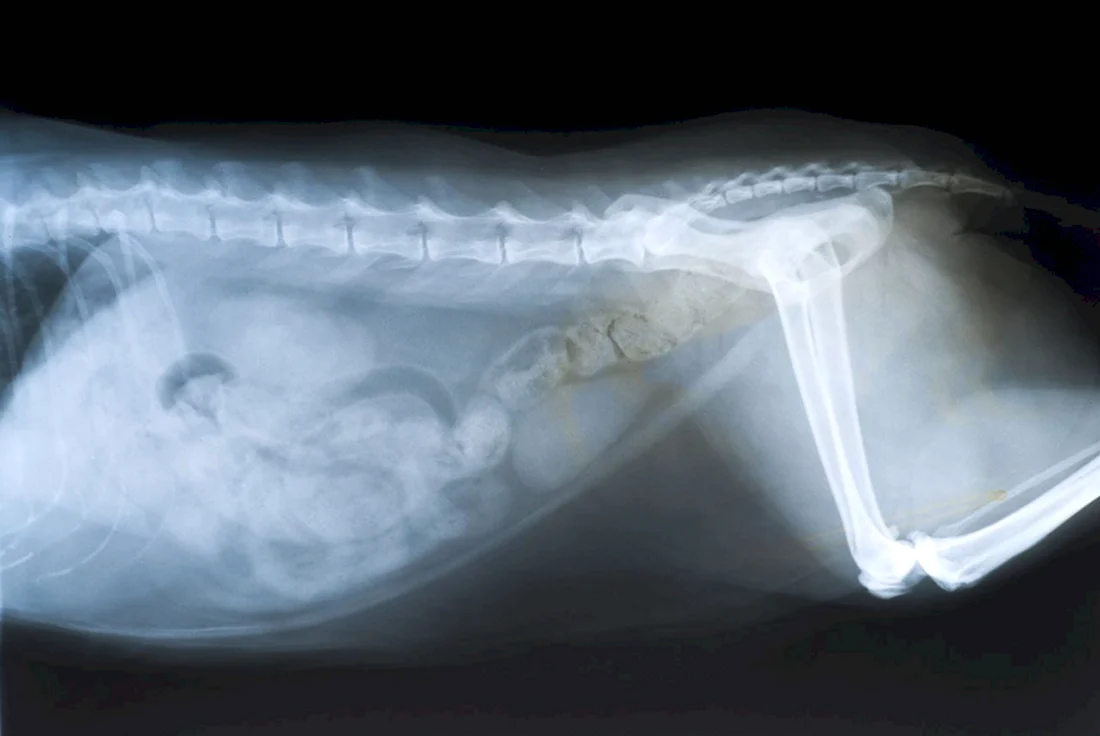

В данной статье представлена уникальная галерея фотографий, которые запечатлевают нежное чудо жизни — котят в утробе кошки. Вас ждут 35 потрясающих фото и картинок, позволяющих заглянуть в мир развивающихся маленьких созданий. Приглашаем вас окунуться в эту удивительную галерею и насладиться прекрасными видами эмбрионов кошачьих детенышей.

Так трогательно и волнующе наблюдать за процессом формирования новой жизни внутри мамы-кошки на этих удивительных фотографиях.